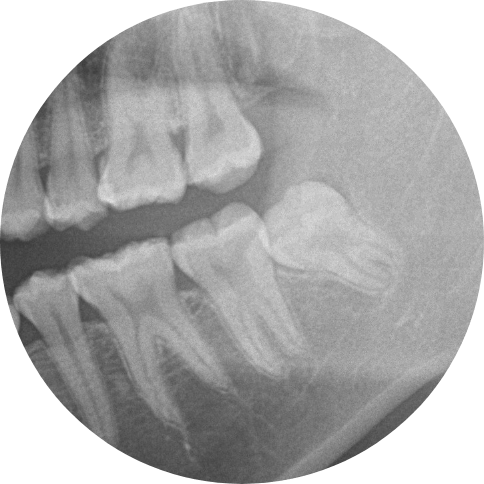

奥歯の歯と歯の間の比較的深い虫歯

1,必要に応じて麻酔を行い十分麻酔が効いた後虫歯を専用のドリルで削って除去していきます。

除去に使用する切削器具はいろいろあり、歯の状態によって都度切削器具を変えて虫歯をとっていきます。

途中痛みが出たりするようであれ麻酔を追加で入れたりしていきます。

なるべく虫歯だけを取り除き最小限の切削で処置していくのが理想ですが取り残さないのが一番大事なことになります

2,特別な神経を保護するお薬を暫間的に入れ込みます。

これにはいろいろ種類があり歯の組成と似たカルシウムを内包した材料が使用されることが多いです。

また最近ではより効果が高い材料も開発されていますが、当院では昔からある信頼性が高い材料を使用しています。

3,一定期間そのまま様子をみて各種症状が出ないようであれば型をとります。

経過観察する期間としては歯の切削状態、Drの考え方、最終的な埋める材質、患者の希望などの要素により一概にどれくらい経過を見ていくかは決まっておりません。

ただこの状態で来院が途絶えると、より深刻な状態になることがるため、必ず最終的なものが入るまでは来院していくことをお勧めしております。

4,作ってきた詰め物を調整後くっつけていきます。

作ってきたものを付けていくときに材質によっては、調整後にくっつけるパターンとくっつけた後に調整するパターンがあります、主に前者は金属を使用した詰め物ときによく見られます。

逆にセラミックを使用した詰め物の時には後者のパターンが多いです。

どちらの処理にしても最終的には綺麗になるので問題はありません。